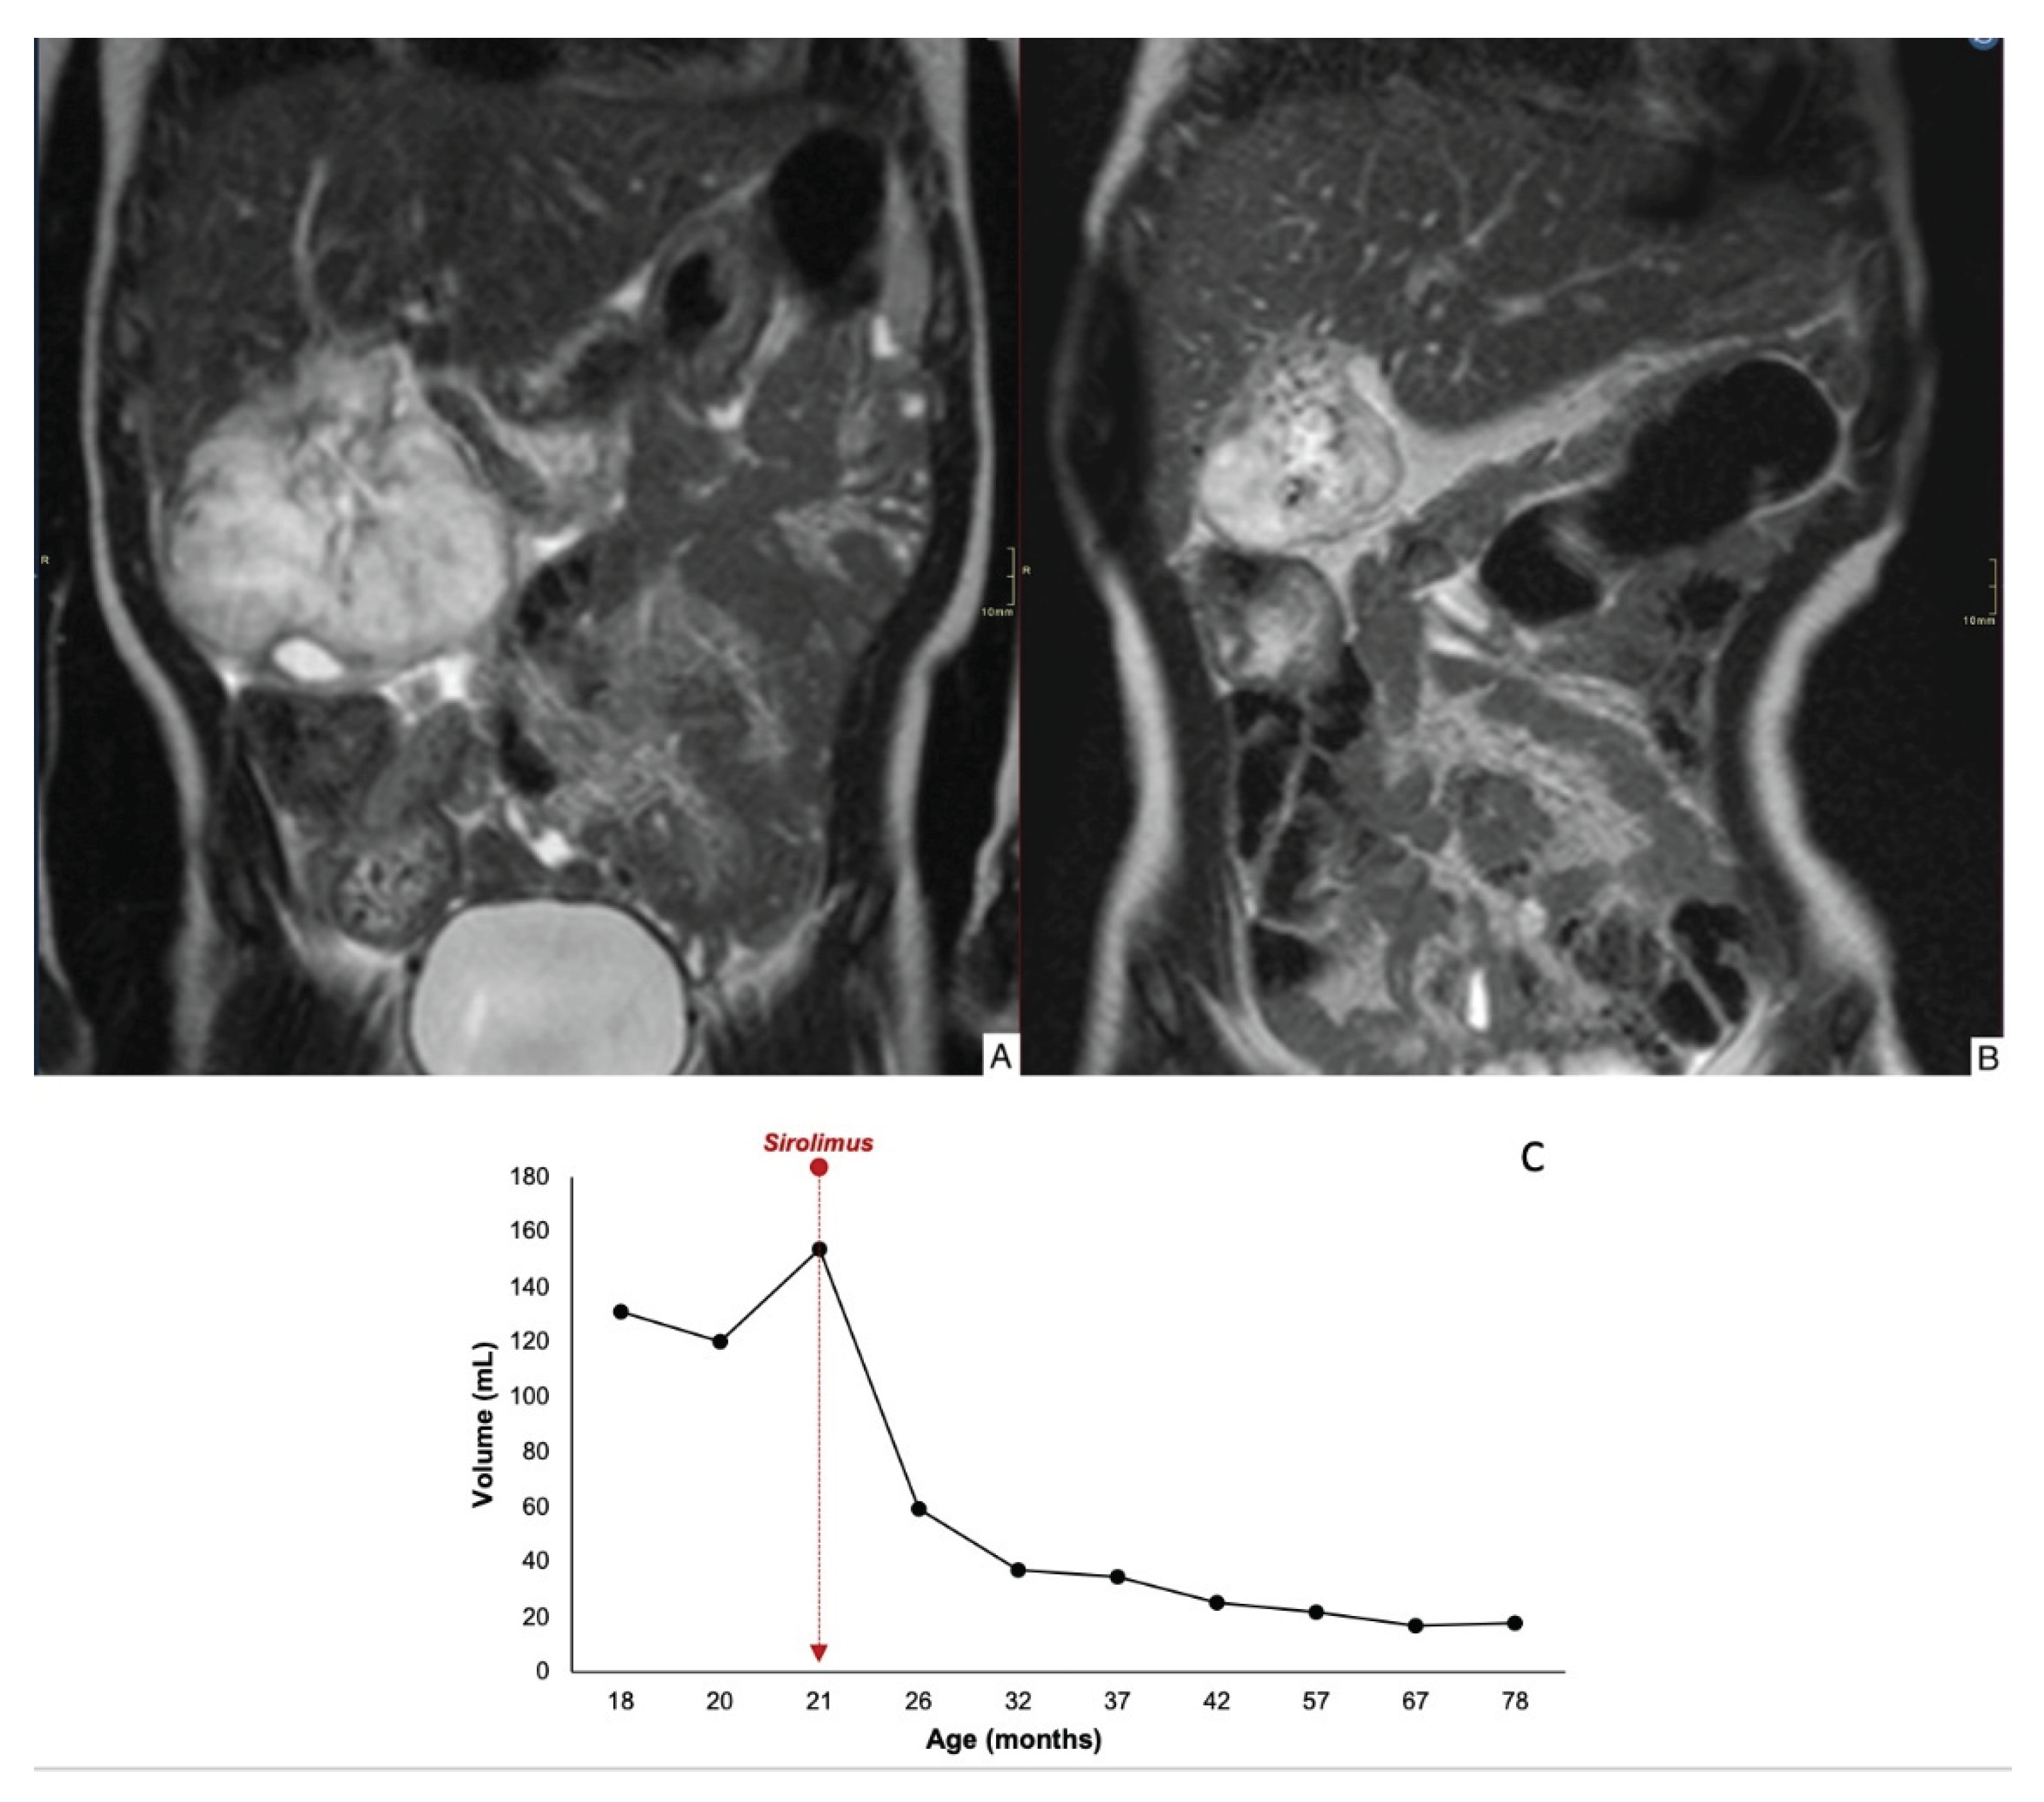

| 1 | 7 x 6 x 6 >4cm |

21 | Partial | 84% | 69 | No | Yes | Propranolol | 79 |